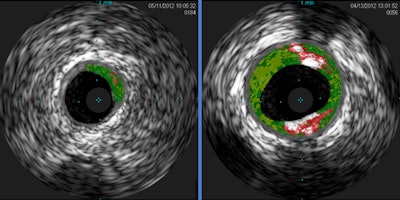

Cross-sectional IVUS images of coronary arteries. Plaque buildup (colored areas) in an artery from a patient who lacks sensitivity to the red meat allergen (left) is much lower than plaque levels in an artery from a patient with sensitivity to the allergen (right). Images courtesy of Dr. Angela Taylor of the University of Virginia Health System."This novel finding from a small group of subjects from Virginia raises the intriguing possibility that allergy to red meat may be an underrecognized factor in heart disease," McNamara said in a statement released by the NIH. "These preliminary findings underscore the need for further clinical studies in larger populations from diverse geographic regions and additional laboratory work."

The investigators analyzed blood samples from 118 adults and found antibodies to alpha-Gal in 26%. Next, they used intravascular ultrasound (IVUS) to analyze the quantity of plaque in the blood samples. The amount was 30% higher in the alpha-Gal-sensitized patients than in the nonsensitized patients.